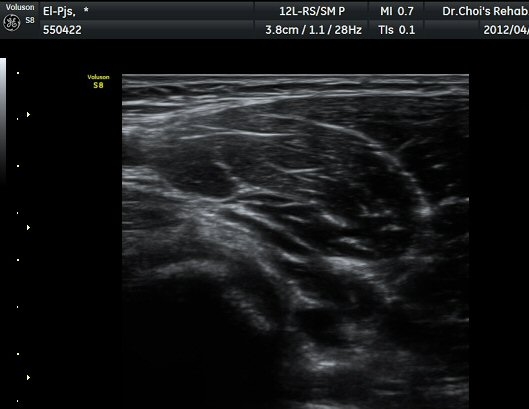

ŽÃËÀÚ¸¦ ÆÈ²ÞÄ¡ ¸»´ÜÀ¸·Î À̵¿ÇÏ´Ï À̵ιڱ٠ÈûÁÙÀÇ ºñÈÄ¿Í ÈûÁÙ ÁÖÀ§¿¡ Àú¿¡ÄÚ ¼ö¾×Àú·ù°¡ ]

°üÂûµÈ´Ù(±×¸² 2, 3, 4, 5). ŽÃËÀÚ¸¦ ¸»´ÜÀ¸·Î À̵¿ÇÒ ¶§ ŽÃËÀÚ¸¦ ¸Ó¸®ÂÊÀ¸·Î °æ»ç(tilting)½ÃÄѾß

À̵ιڱ٠ÈûÁÙ¿¡ Á÷°¢ ÀÇ ÃÊÀ½ÆÄ Á¶»ç°¡ °¡´ÉÇÏ¿© À̵ιڱ٠ÈûÁÙÀÌ °í¿¡ÄÚ·Î °üÂûµÈ´Ù.

À̵ιڱ٠ÈûÁÙ Á¾´Ü¸é°Ë»ç¿¡¼­ ÈûÁÙÀÇ ºñÈİ¡ °üÂûµÇ³ª ÈûÁÙÀÇ ¿ä°ñµ¹±â(radial tuberosity)

ºÎÂøºÎ´Â ºñµî¹æ¼ºÀΰøÀ½¿µ(anisotopic artifact) ¶§¹®¿¡ ¶Ñ·ÈÈ÷ °üÂûµÇÁö ¾Ê´Â´Ù(±×¸² 6).